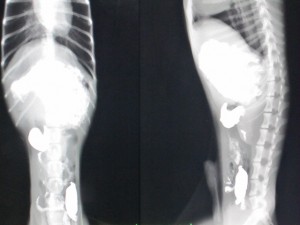

レントゲン

バリウム投与24時間後のレントゲン。

胃内にバリウムがまだたくさん残っています。

内視鏡でも確認しましたが、今回は胃切開が適応となりました。